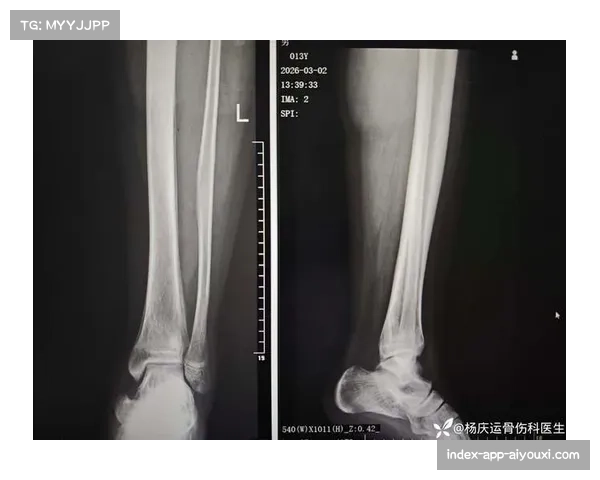

朱旭航自去年遭遇胫骨骨折以来,恢复进展一直备受关注。尽管他在康复过程中展现出极大的毅力,但伤病的复杂性使得回归赛场的时间一再推迟。新疆队在签下朱旭航时,寄希望于他的经验和技术能够提升球队实力。然而,长时间的缺阵不仅让球队在战术安排上捉襟见肘,也使得管理层面临巨大的经济压力。